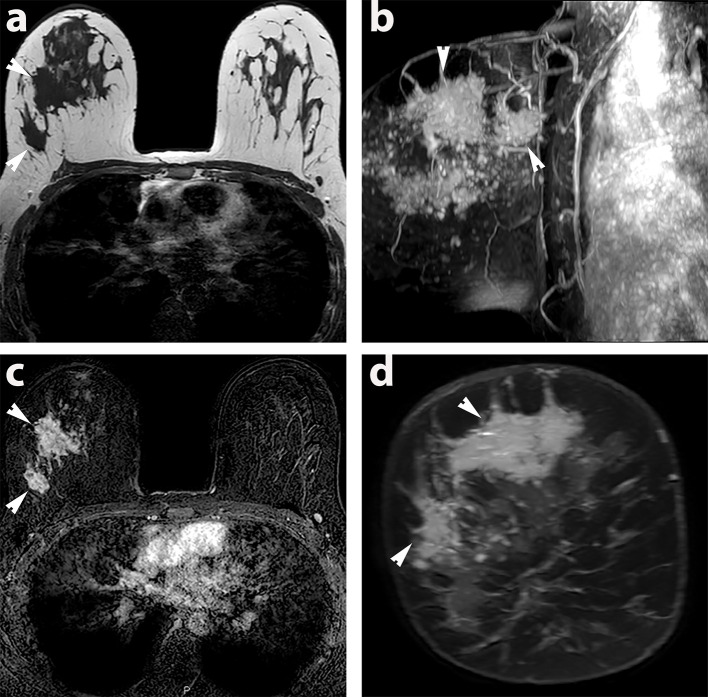

超极化 13C 磁共振成像(HP-MRI)是一种新型成像技术,可对体内代谢途径进行实时分析1 。随着分子生物学知识的发展,人们越来越清楚地认识到癌细胞代谢与疾病结果的关系,其中乳酸引起了特别关注。2 近期对乳腺癌筛查项目的审查引起了人们的关注,并提高了公众对过度治疗的认识。科学界需要将重点从单纯提高癌症检测率转移到寻求新的方法来区分侵袭性乳腺癌和仍将保持不扩散的乳腺癌。HP-MRI 为识别侵袭性肿瘤表型和帮助监测/预测治疗反应提供了机会。在此,我们报告了首例使用 HP-MRI 和包括乳腺 MRI 在内的相关传统成像技术进行成像的乳腺癌病例。

Hyperpolarised 13C MRI (HP-MRI) is a novel imaging technique that allows real-time analysis of metabolic pathways in vivo.1 The technology to conduct HP-MRI in humans has recently become available and is starting to be clinically applied. As knowledge of molecular biology advances, it is increasingly apparent that cancer cell metabolism is related to disease outcomes, with lactate attracting specific attention. 2 Recent reviews of breast cancer screening programs have raised concerns and increased public awareness of over treatment. The scientific community needs to shift focus from improving cancer detection alone to pursuing novel methods of distinguishing aggressive breast cancers from those which will remain indolent. HP-MRI offers the opportunity to identify aggressive tumour phenotypes and help monitor/predict therapeutic response. Here we report one of the first cases of breast cancer imaged using HP-MRI alongside correlative conventional imaging, including breast MRI.